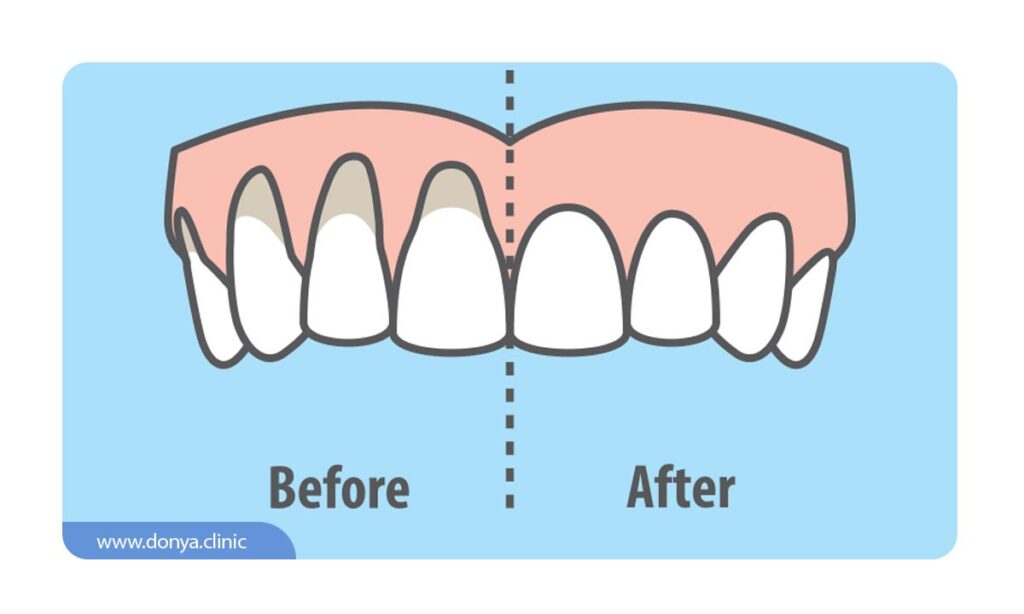

تحلیل لثه یا (Gum recession) نوع رایجی از مشکلات دندانپزشکی است که در آن، حاشیه بافت لثه (که دندان ها را احاطه کرده) از بین رفته یا نازک می شود. اصطلاحاً به این مشکل عقب نشینی لثه نیز گفته می شود. زمانی که لثه تحلیل می رود، ریشه دندان ها نمایان می شود و مشکلات زیادی برای افراد ایجاد می شود.

اولین علامت عقب نشینی لثه معمولاً حساسیت دندان است. به جز این ممکن است متوجه شوید ریشه دندان در معرض دید قرار گرفته یا طول دندان کمی بیشتر از چیزی شده که قبلا بود.

- منقبض شدن مشهود لثه ها که در آن لثه ها به نظر کوچک تر و دندان ها بلندتر به نظر می رسند.

- مشخص شدن ریشه های دندان که توسط لثه پوشیده می شوند.

تحلیل خفیف لثه احتمالا توسط دندانپزشک و با روش هایی مانند جرم گیری دندان از بین می رود و خود به خود ترمیم می شود. در طی جرم گیری که به آن فرآیند اسکیلینگ و روت پلنینگ گفته می شود. پلاک، تارتار و جرم دندانی که به زیر خط لثه رسیده از بین برده می شوند. همچنین برای از بین بردن سایر باکتری ها و عفونت های باقی مانده آنتی بیوتیک تزریق می شود. اما اگر رکود لثه به قدری زیاد باشد که به استخوان و دندان آسیب رسیده باشد با جرم گیری دندان نمی توان مشکل را برطرف کرد و باید برای ترمیم ساختارهای آسیب دیده مداخلات دندانپزشکی بیشتری در نظر گرفت.